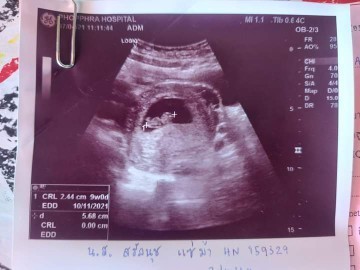

รูป ตอนที่ท้องได้ 9 w จ้ะ

Post reply image